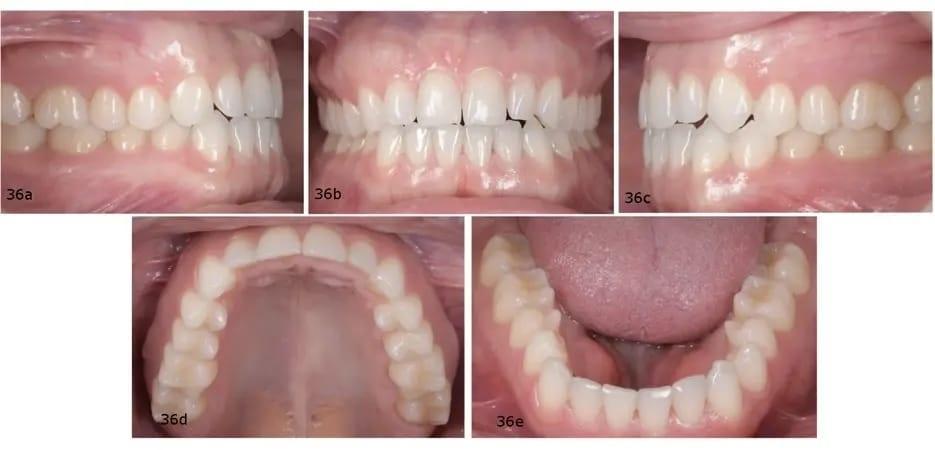

Панорамная рентгенограмма показала предварительное удаление всех третьих моляров, локальную резорбцию корней нескольких зубов, в целом хорошее состояние пародонта и атипичную морфологию мыщелков, свидетельствующую о ремоделировании височно-нижнечелюстного сустава (ВНЧС) или дегенеративных изменениях (фото 19). Цефалометрическая рентгенограмма и трассировка выявили мезобрахиально-лицевой тип скелета и тенденцию к формированию скелета II класса (фото 20).

Фото 19: Дооперационная панорамная рентгенограмма.